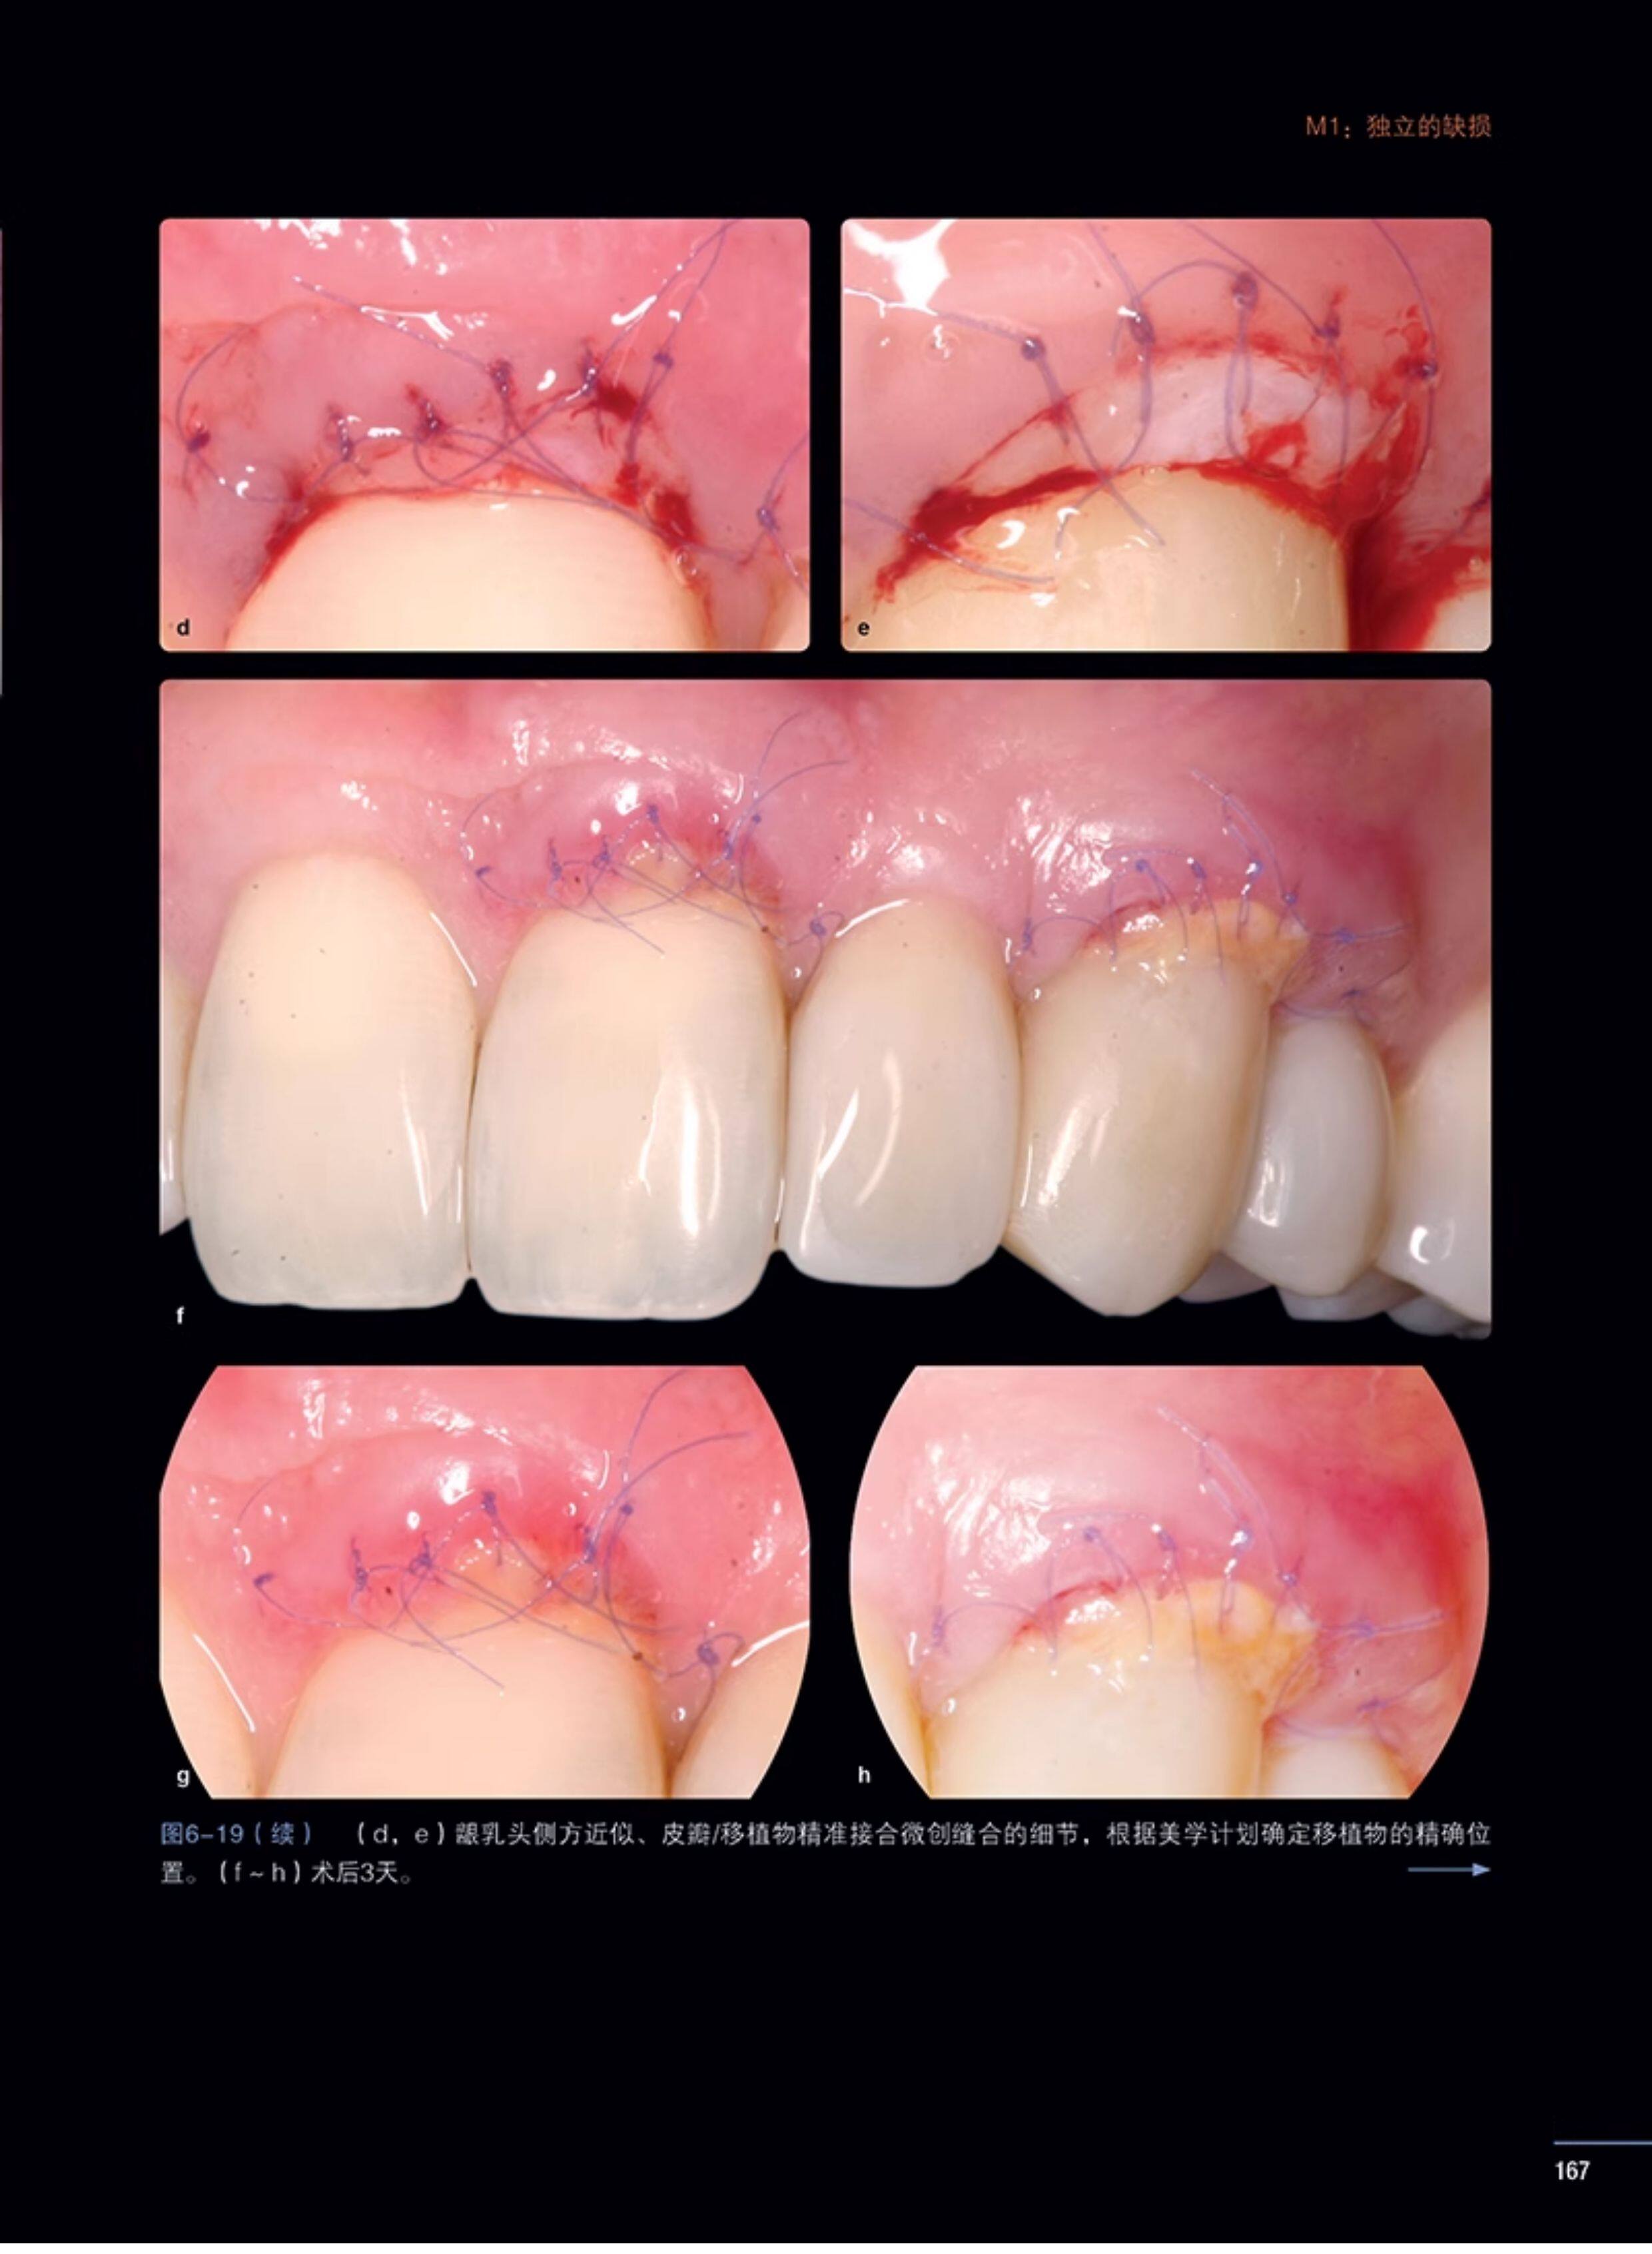

书名:牙周及种植体周显微整形外科图谱

本书介绍的内容涵盖微创手术,同时系统讲解了显微外科技术、软组织缺损的解决方案,以及这些显微外科原理与种植手术的关联。本书还介绍了为达到美学目的的数字化美学设计和冠延长显微外科处置,以及对使用显微镜医生的健康、舒适度和生活质量相关的人体工程学设计。